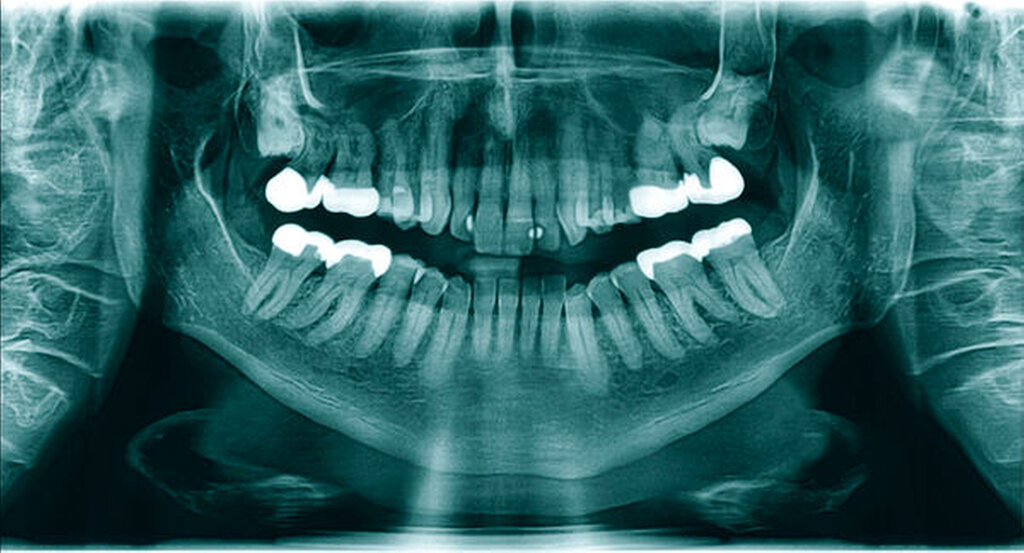

Die Therapie der chronischen Sinusitiden blieb erfolglos, so dass der Patient an täglicher, beidseitiger Exkretion grünlichen Sekrets aus den Nasenlöchern sowie chronischen Kopfschmerzen litt. Dental waren alle Oberkieferzähne klinisch unauffällig und vital. Zum Ausschluss einer klinisch okkulten dentogenen Ursache der chronischen Sinusitis maxillaris und zur Beurteilung der Lage der retinierten Zähne 18 und 28 wurde eine Panoramaschichtaufnahme (PSA) erstellt.

Nebenbefundlich zeigte sich in der PSA (Abbildung 1) im Bereich des rechten Kieferastes eine circa 10 mm x 6 mm große, klar begrenzte, knochendichte Opazität. Diese Opazität erschien als am Rand opak verdichtete und nicht infiltrierende Struktur, die mit keiner erkennbaren dentogenen oder nicht-dentogenen Struktur direkt korrelierte. Auf einer zum Vergleich vom Hauszahnarzt angeforderten PSA, die etwa neun Jahre zuvor erstellt wurde, ist ein vergleichbarer Befund zu sehen (Abbildung 2).